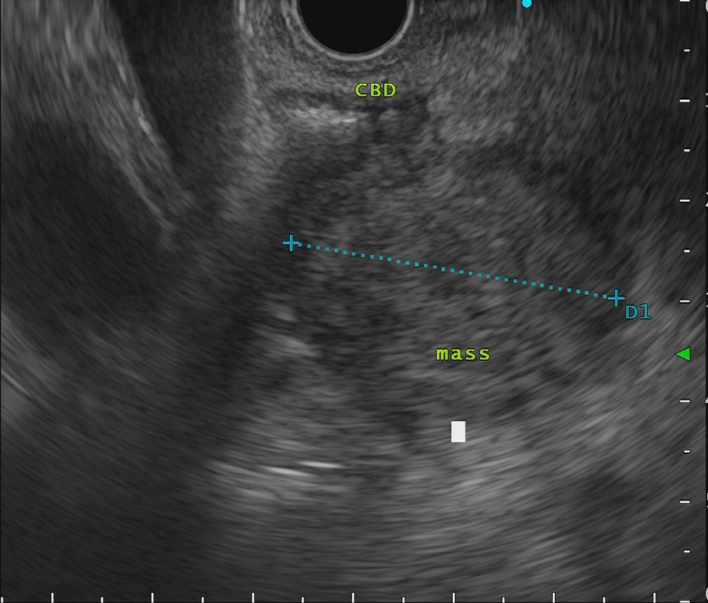

- 超音波内視鏡

術前シミュレーション画像(CT画像)

術前の検討